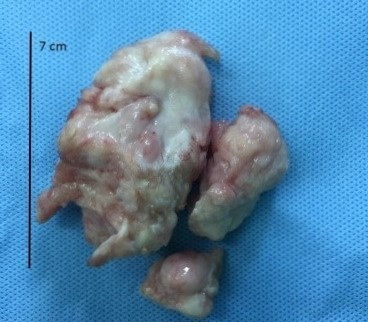

| Khối u trong tim bé được bác sĩ bóc tách thành công. Ảnh: Nam Phương |

Các bác sĩ đã loại bỏ khối u an toàn, giúp duy trì chức năng sinh sản và nâng cao chất lượng cuộc sống cho bệnh nhi 14 tuổi mắc ung thư buồng trứng hiếm gặp.